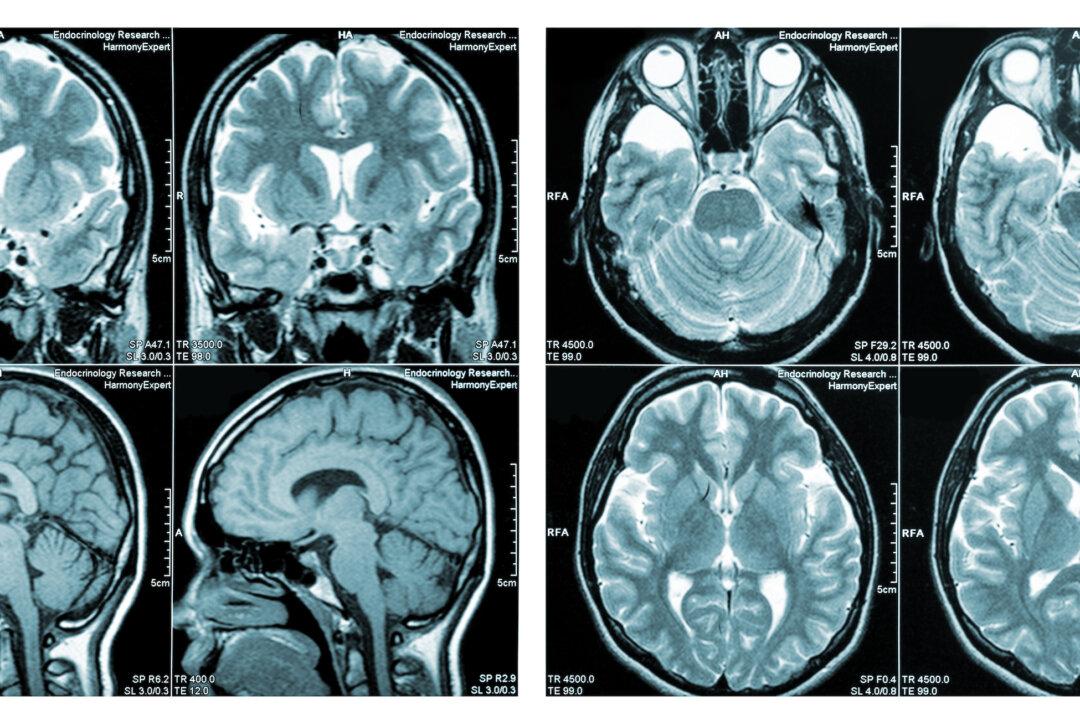

We have 86 billion neurons in the human brain, and each of those connects with 10,000 other neurons. No other structure in the known universe rivals the brain’s complexity.The brain is also the most exclusive club, so to speak, in the body. The gatekeeper is the blood-brain barrier (BBB). That barrier, shown in the second illustration below, is mostly composed of tight junctions between endothelial cells that line, in a single layer, the capillaries (our smallest blood vessels) that nourish the brain. So the BBB is in effect the capillary walls and the tight junctions between its cells.